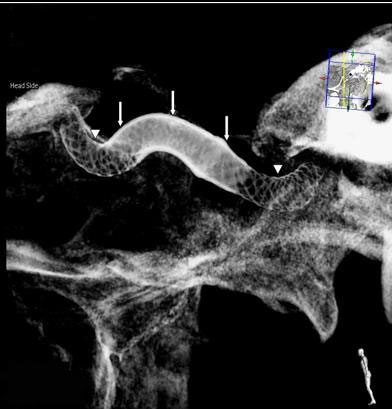

A diagnostic spinal angiography is a medical procedure that offers an extremely precise evaluation of the blood vessels surrounding the spinal cord.

Spinal angiography helps diagnosing medical conditions that involve the arteries and veins of the spinal cord. This typically includes spinal cord vascular malformations, such as dural arteriovenous fistulas (DAVF) and arteriovenous malformations (AVM), but also certain types of spinal cord stroke and disorders involving the spinal cord venous system, such as spinal venous thrombosis